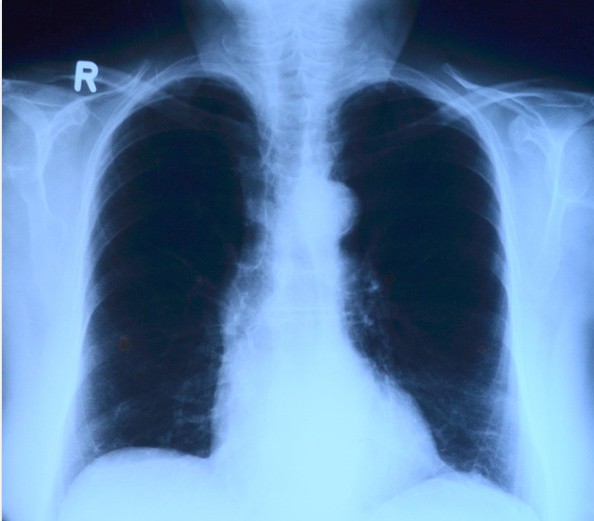

②胸部X线检查用透视、后前位胸片、前弓位摄片、点片、肺尖部摄片、断层摄片。

除以上检查外,肺结核病人还要做CT检查等。有时肺结核病人还需要做更为全面的检查,以便发现还有没有其他与此相关的疾病。